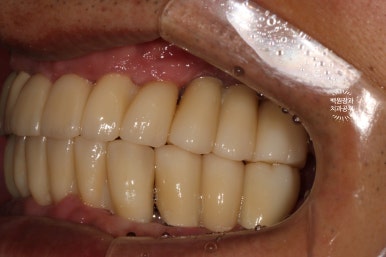

시간이 지나.. 최종 보철물을 만들어드리는 시간입니다.

약 한달간의 씹는 연습을 마치게 되면, 이제 본격적으로 최종 보철물을 제작해드리게 됩니다.

지르코니아 재질로 만들어진 크라운은 심미적으로도 유리하며, 그 단단함은 성인 남성이 넉넉히 사용하여도 깨지지 않을 정도에요.

치아 색이 약간 노랗다 생각하실수도 있으나, 피부색에 맞추어 제작되므로 너무 걱정하진 마세요!

오히려 너무 밝은 하얀 치아가 어색한 분도 많이 있으시기 때문입니다.

이렇게 보면 측면 모습도 상당히 괜찮고....

잘 보시면 치아와 치아 사이에 틈이 있는 것을 보실 수 있으실텐데요, 이 경계는 앞니 보철물/어금니 보철물의 경계로 추후에 보철물의 수리가 용이하기 하기 위함입니다. 더불어 치실을 쓸 수 있게 하는 공간으로 반드시 필요한 포인트!

이젠 치아가 생겨서, 식사를 하실 수 있게 되었습니다.

잘 제작된 보철물은 앞니로 면도 끊어먹을 수 있어서 환자분들께 크나큰 만족감을 줍니다.